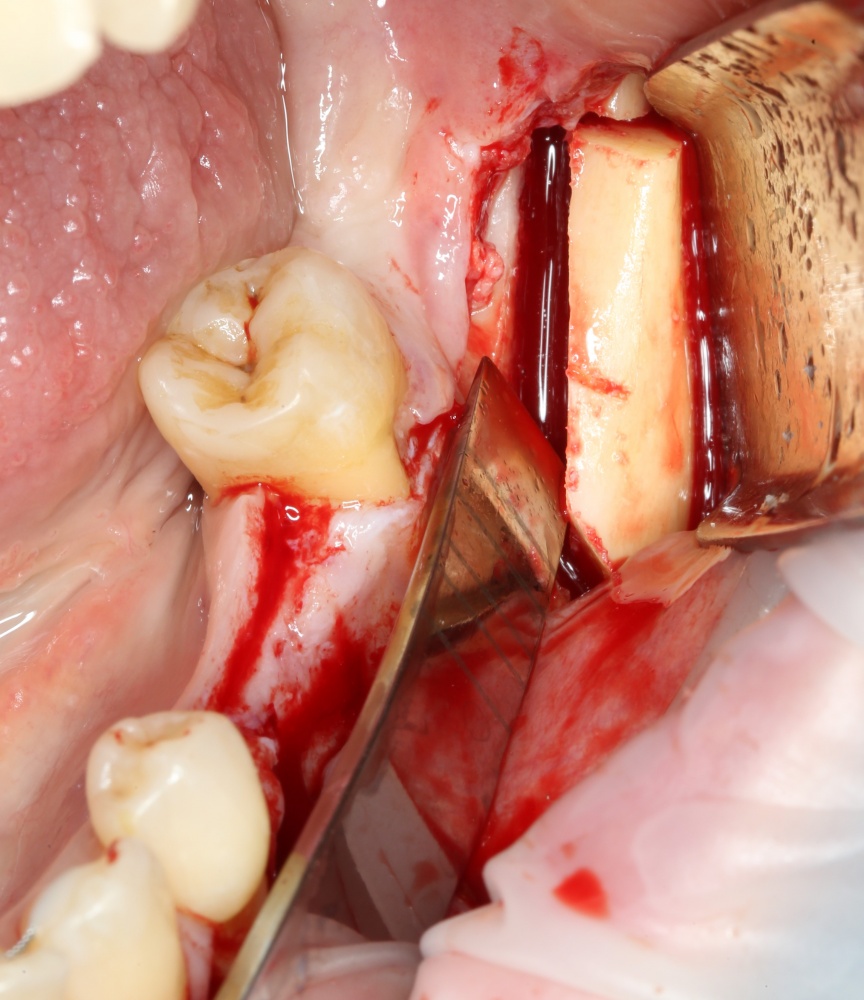

Имплантация и остеопластика (наращивание костной ткани): вместе или врозь? Часть I.